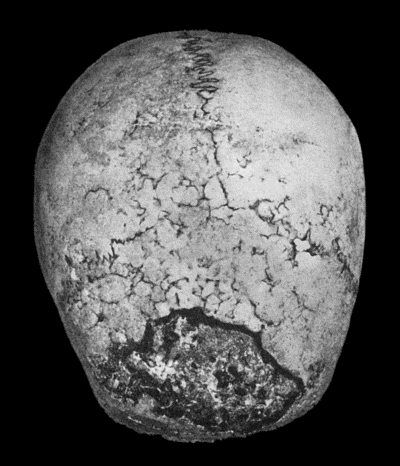

| 134. | Changes in the Skull resulting from Ostitis Deformans | 474 |

| 135. | Cadaver, illustrating the alterations in the Lower Limbs resulting from Ostitis Deformans | 475 |